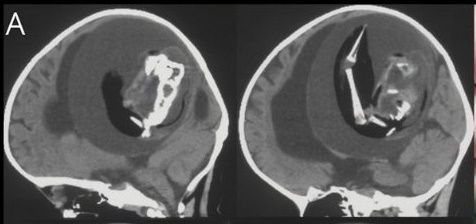

10일 홍콩01 등 현지 언론에 따르면 지난해 12월 신경학 저널에 중국 푸단 대학 병원 의사들이 1세 여아 두개골 안에서 일란성 쌍둥이 기생 태아를 제거했다는 사례가 보고됐다.

당초 아이는 대두증과 운동 능력 상실을 이유로 부모와 함께 병원을 방문했다. 의료진은 아이 머리에 단순 종양이 있다고 판단해 CT(컴퓨터 단층 촬영)를 찍었다. 하지만 의료진 예상과 정반대의 결과가 나왔다. 아이 두개골에서 태아가 발견된 것이다.

두개골 속 태아는 웅크린 채 뇌를 짓누르고 있었다. 아이와 연결된 혈관으로부터 양분을 공급받아 뼈와 팔, 손까지 발달한 상태였다. 아이는 두개골에 자리를 차지하고 있는 태아로 인해 뇌 일부분에 척수액이 고이는 수두증(물뇌증)을 앓고 있었다.

의료진은 즉시 기생 태아를 두개골에서 제거했다. DNA 분석 결과 해당 태아는 아이의 쌍둥이였던 것으로 조사됐다. 도태돼야 하는 분리된 수정란이 전뇌로 발달하면서 이 같은 사례가 발생한 것이다.